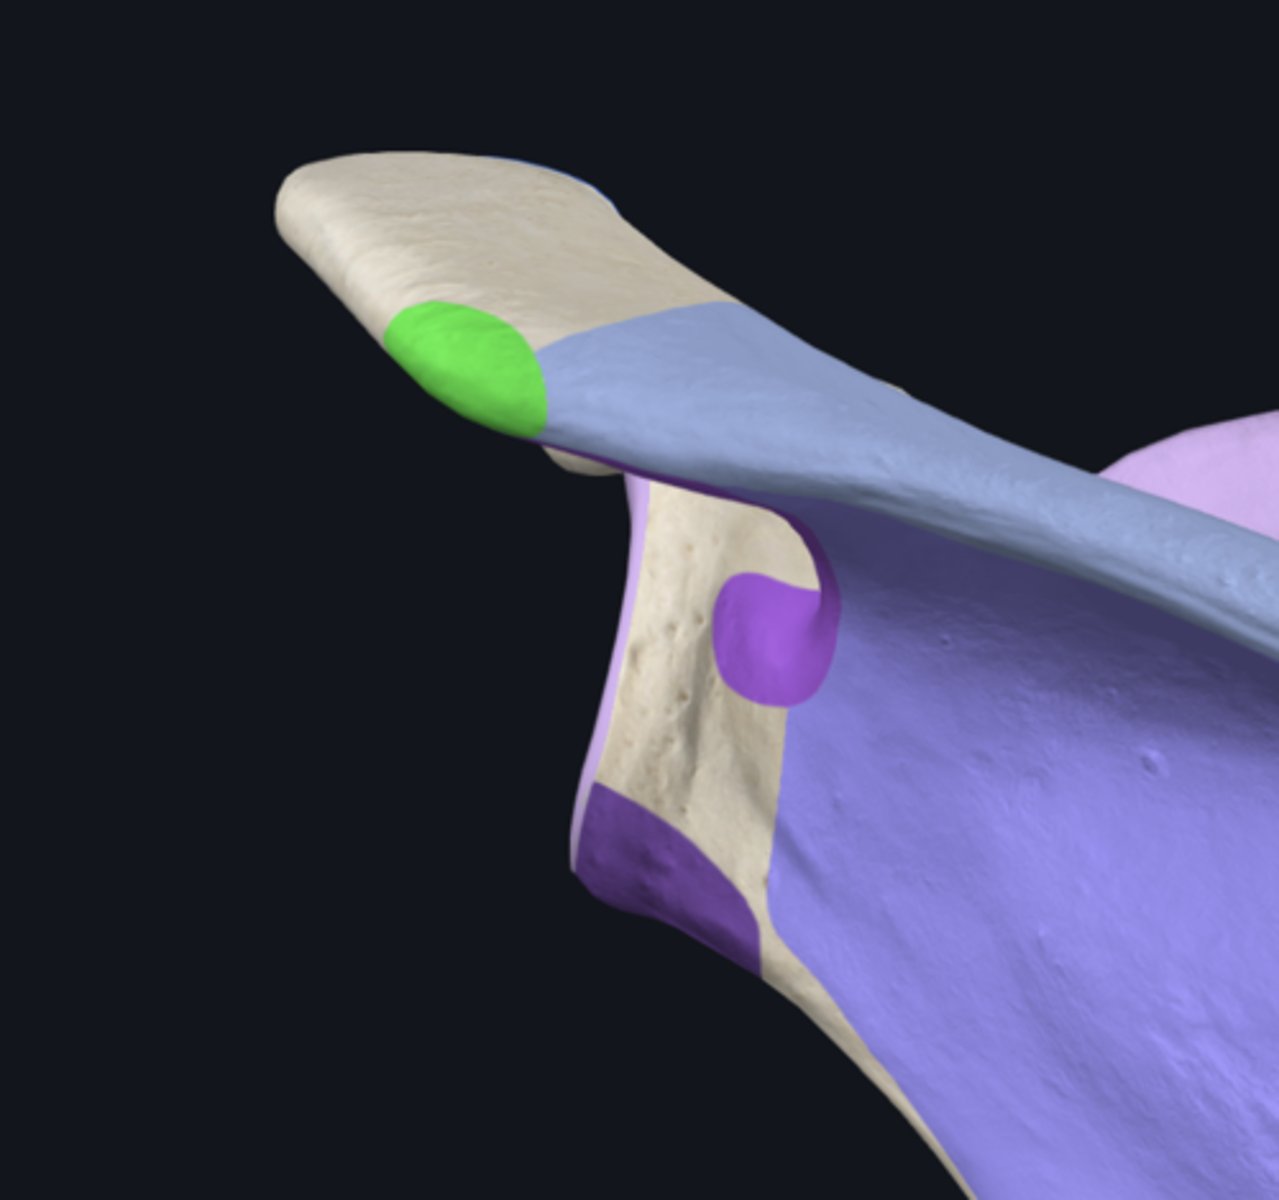

acromial end

body of clavicle

sternal end

acromial facet

conoid tubercle

groove for subclavius muscle

impression for costoclavicular ligament

sternal articular surface

trapezoid line